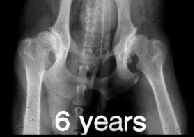

RTG snímek se provádí v tzv. extenzní ventrodorzální

projekci. Znamená to, že se psí pacient rentgenuje ve hřbetní poloze s

nataženými pánevními končetinami navzájem rovnoběžně dozadu. K

dokonalému napolohování psa se používá zvláštní lůžko ve tvaru písmene

"V" na průřezu.

Pro objektivní posouzení DKK by měl být snímek

symetrický, jelikož špatně zhotovený snímek může vést k chybné

interpretaci nálezu. Na snímku by tedy měla být zachycena celá pánev,

kost křížová a obě stehenní kosti včetně kolenních kloubů, pouze u

velkých a obřích plemen je dovoleno posunout pánev tak, že na snímku

nejsou vidět obě pately (čéšky). Stehenní kosti by měly probíhat

rovnoběžně mezi sebou a součastně s podélnou osou těla.

ŠPATNĚ PROVEDENÝ RTG SNÍMEK!!

Projekce není symetrická - stehenní kosti a podélná

osa těla nejsou rovnoběžné. |